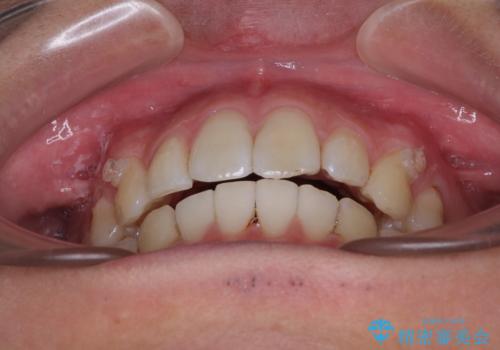

前歯のデコボコをインビザラインで綺麗に改善

- 上下前歯のデコボコとクロスバイトを気にして来院された患者様です。

インビザラインを用い、IPR(歯と歯の間を削る)と歯列全体を拡大させることで、歯並びを整えていくこととしました。

毎日22時間の装着時間を徹底してくださったのですが、左右ともに臼歯が咬合しなくなるという、インビザライン独特の症状が強く長く続いてしまい、終了するまでに長期間を要してしまいました。